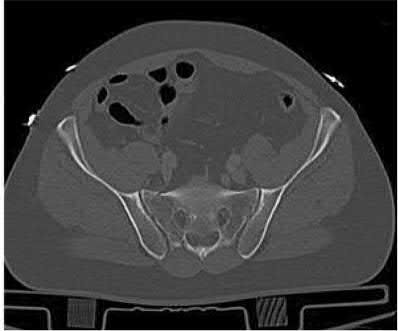

Which of the following images shows an injury pattern most consistent with a lateral compression type 3 pelvic ring injury?

Figure C is an axial CT scan of a lateral compression type 3 (LC3) pelvic ring injury.

Classically, LC3 injuries demonstrate an ipsilateral lateral compression and a contralateral APC (windswept pelvis) fracture pattern. The most common mechanism of injury in these cases is a rollover MVC or pedestrian vs. auto. LC1 injuries are characterized by an oblique or transverse ramus fracture and ipsilateral anterior sacral ala compression fracture, while LC2 injuries consist of a rami fracture and ipsilateral posterior ilium fracture dislocation (crescent fracture). While LC1 injuries can often initially be managed conservatively with protected weight-bearing and close observation, LC2 and LC3 pelvic ring injuries are almost universally operative.

Answer 1: This represents a lateral compression type 2 injury. Answer 2: This represents a lateral compression type 1 injury.

Answer 4: This represents an anterior posterior compression type 2 injury. Answer 5: This represents an anterior posterior compression type 3 injury.